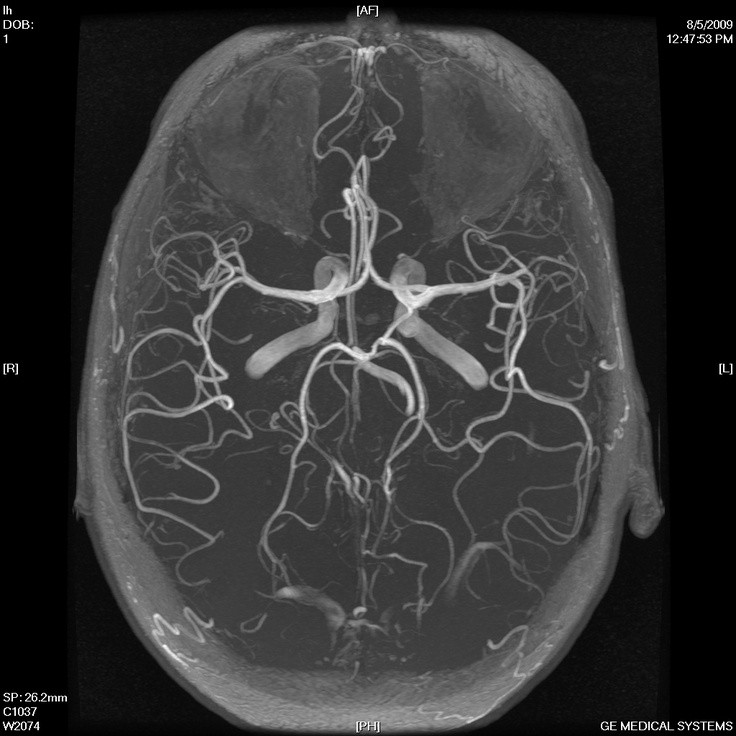

Pretirana ograjenost od okolice lahko pogosto vodi v kopičenje problemov. Podobno velja tudi za človeške možgane, ki so obdani s krvno–možgansko pregrado. Kljub njeni zaščitni vlogi, predstavlja ta glavno oviro v dostavljanju zdravil do možganov. Zdravljenje možganskih tumorjev, Alzheimerja in drugih bolezni je zato izredno težko, saj številna zdravila ne morejo preiti pregrade.

Preboj v dostavi zdravil preko krvno-možganske bariere je dosegla kanadska skupina raziskovalcev pod vodstvom doktorja Mainprizea. To so dosegli s pomočjo zračnih mehurčkov, vbrizganih v kri bolnice. Ko so ti pripotovali do možganov, so jih raziskovalci obstreljevali z ultrazvokom, zaradi česar so se mehurčki začeli raztezati in krčiti.

Zaradi pulziranja mehurčkov so se na krvno–možganski pregradi ustvarile majhne rane, oziroma luknje, skozi katere so nato lahko prehajala zdravila. Nastale luknjice so bile tudi zadosti majhne, da so se poškodbe zacelile po dvanajstih urah. Metoda se je skratka že izkazala za uspešno.

Če bo metoda prišla v redno uporabo, se obetajo številne nove možnosti za zdravljenje možganskih bolezni, ki jih do sedaj z zdravili ni bil mogoče ciljati.